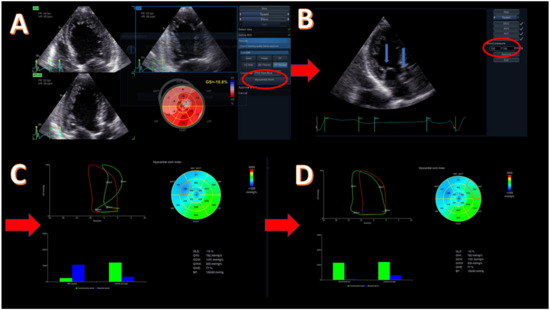

5. Cardiac Dyssynchrony